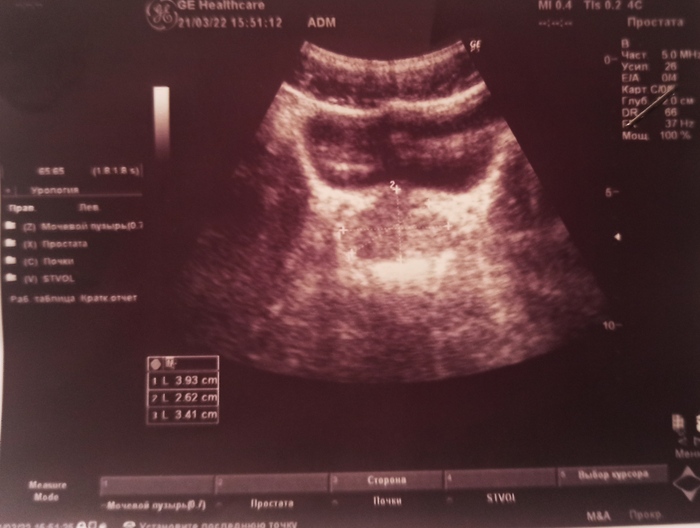

Простатит хронический

Здравствуйте. Прошу знающих людей пояснить результаты на снимке.

Обратился к урологу в частной клинике. Из жалоб лишь частое мочеиспускание (болей/резей едва ли ощущаю). УЗИст сделал вывод, что недуг прогрессирует уже как несколько лет. С тем же согласилась и уролог.

Назначила антибиотики внутривенно/внутримышечно и в таблетках, противогрибковый препарат в капсулах и физиотерапию.

насколько адекватно такое лечение?

странно, что не припоминаю никаких сильных болей или дискомфорта в паху